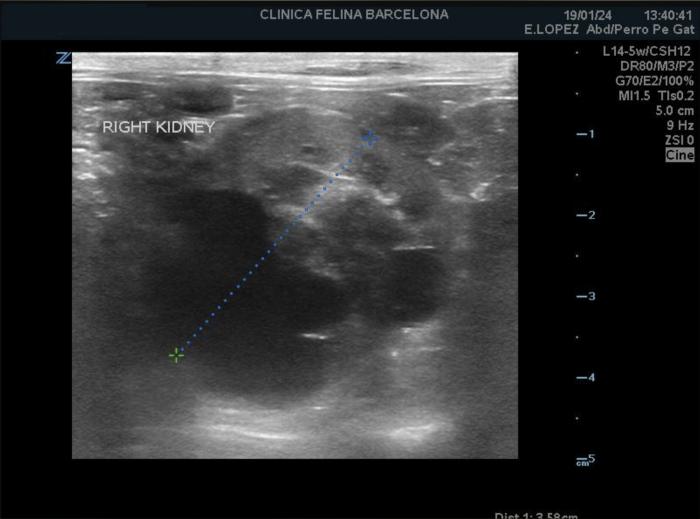

En la ecografía abdominal se visualizaron los dos riñones con contorno irregular. Tanto en la corteza como en la médula de ambos riñones se distinguieron múltiples estructuras redondeadas y anecoicas, de tamaño variable, compatibles con quistes (Figura1 y 2).

La ecografía es la herramienta diagnóstica más práctica en individuos adultos. En la fase inicial de la enfermedad, resulta complicado identificar quistes de pequeño tamaño, sobre todo si su diámetro es inferior a 2 mm (3). La sensibilidad aumenta en función de la edad, siendo del 75 % cuando se realiza a las 16 semanas de edad y del 91 % a las 36 semanas. La especificidad se estima del 100 %, aunque depende sobre todo de la experiencia del ecografista (1). Se ha visto que la ausencia de quistes en la ecografía a los 6 meses de edad se asocia con la ausencia de ERP en la necropsia (4).

Ecográficamente, los quistes se visualizan como estructuras redondas u ovaladas, de tamaño variable (desde menos de 1 mm hasta más de 1 cm), con la pared fina y contenido anecoico con fuerte refuerzo acústico posterior. La mayoría se localizan en la corteza y en la unión corticomedular de uno o ambos riñones. Con el paso del tiempo, los quistes aumentan en número y volumen, sustituyendo el parénquima normal e incluso llegando a deformar el contorno renal. En algunos casos se pueden desarrollar quistes en el hígado y/o páncreas (4)(6)(8) (Figura 4). En nuestro paciente, ecográficamente se observaron ambos riñones irregulares y con quistes, sin lesiones en hígado ni tampoco en páncreas.